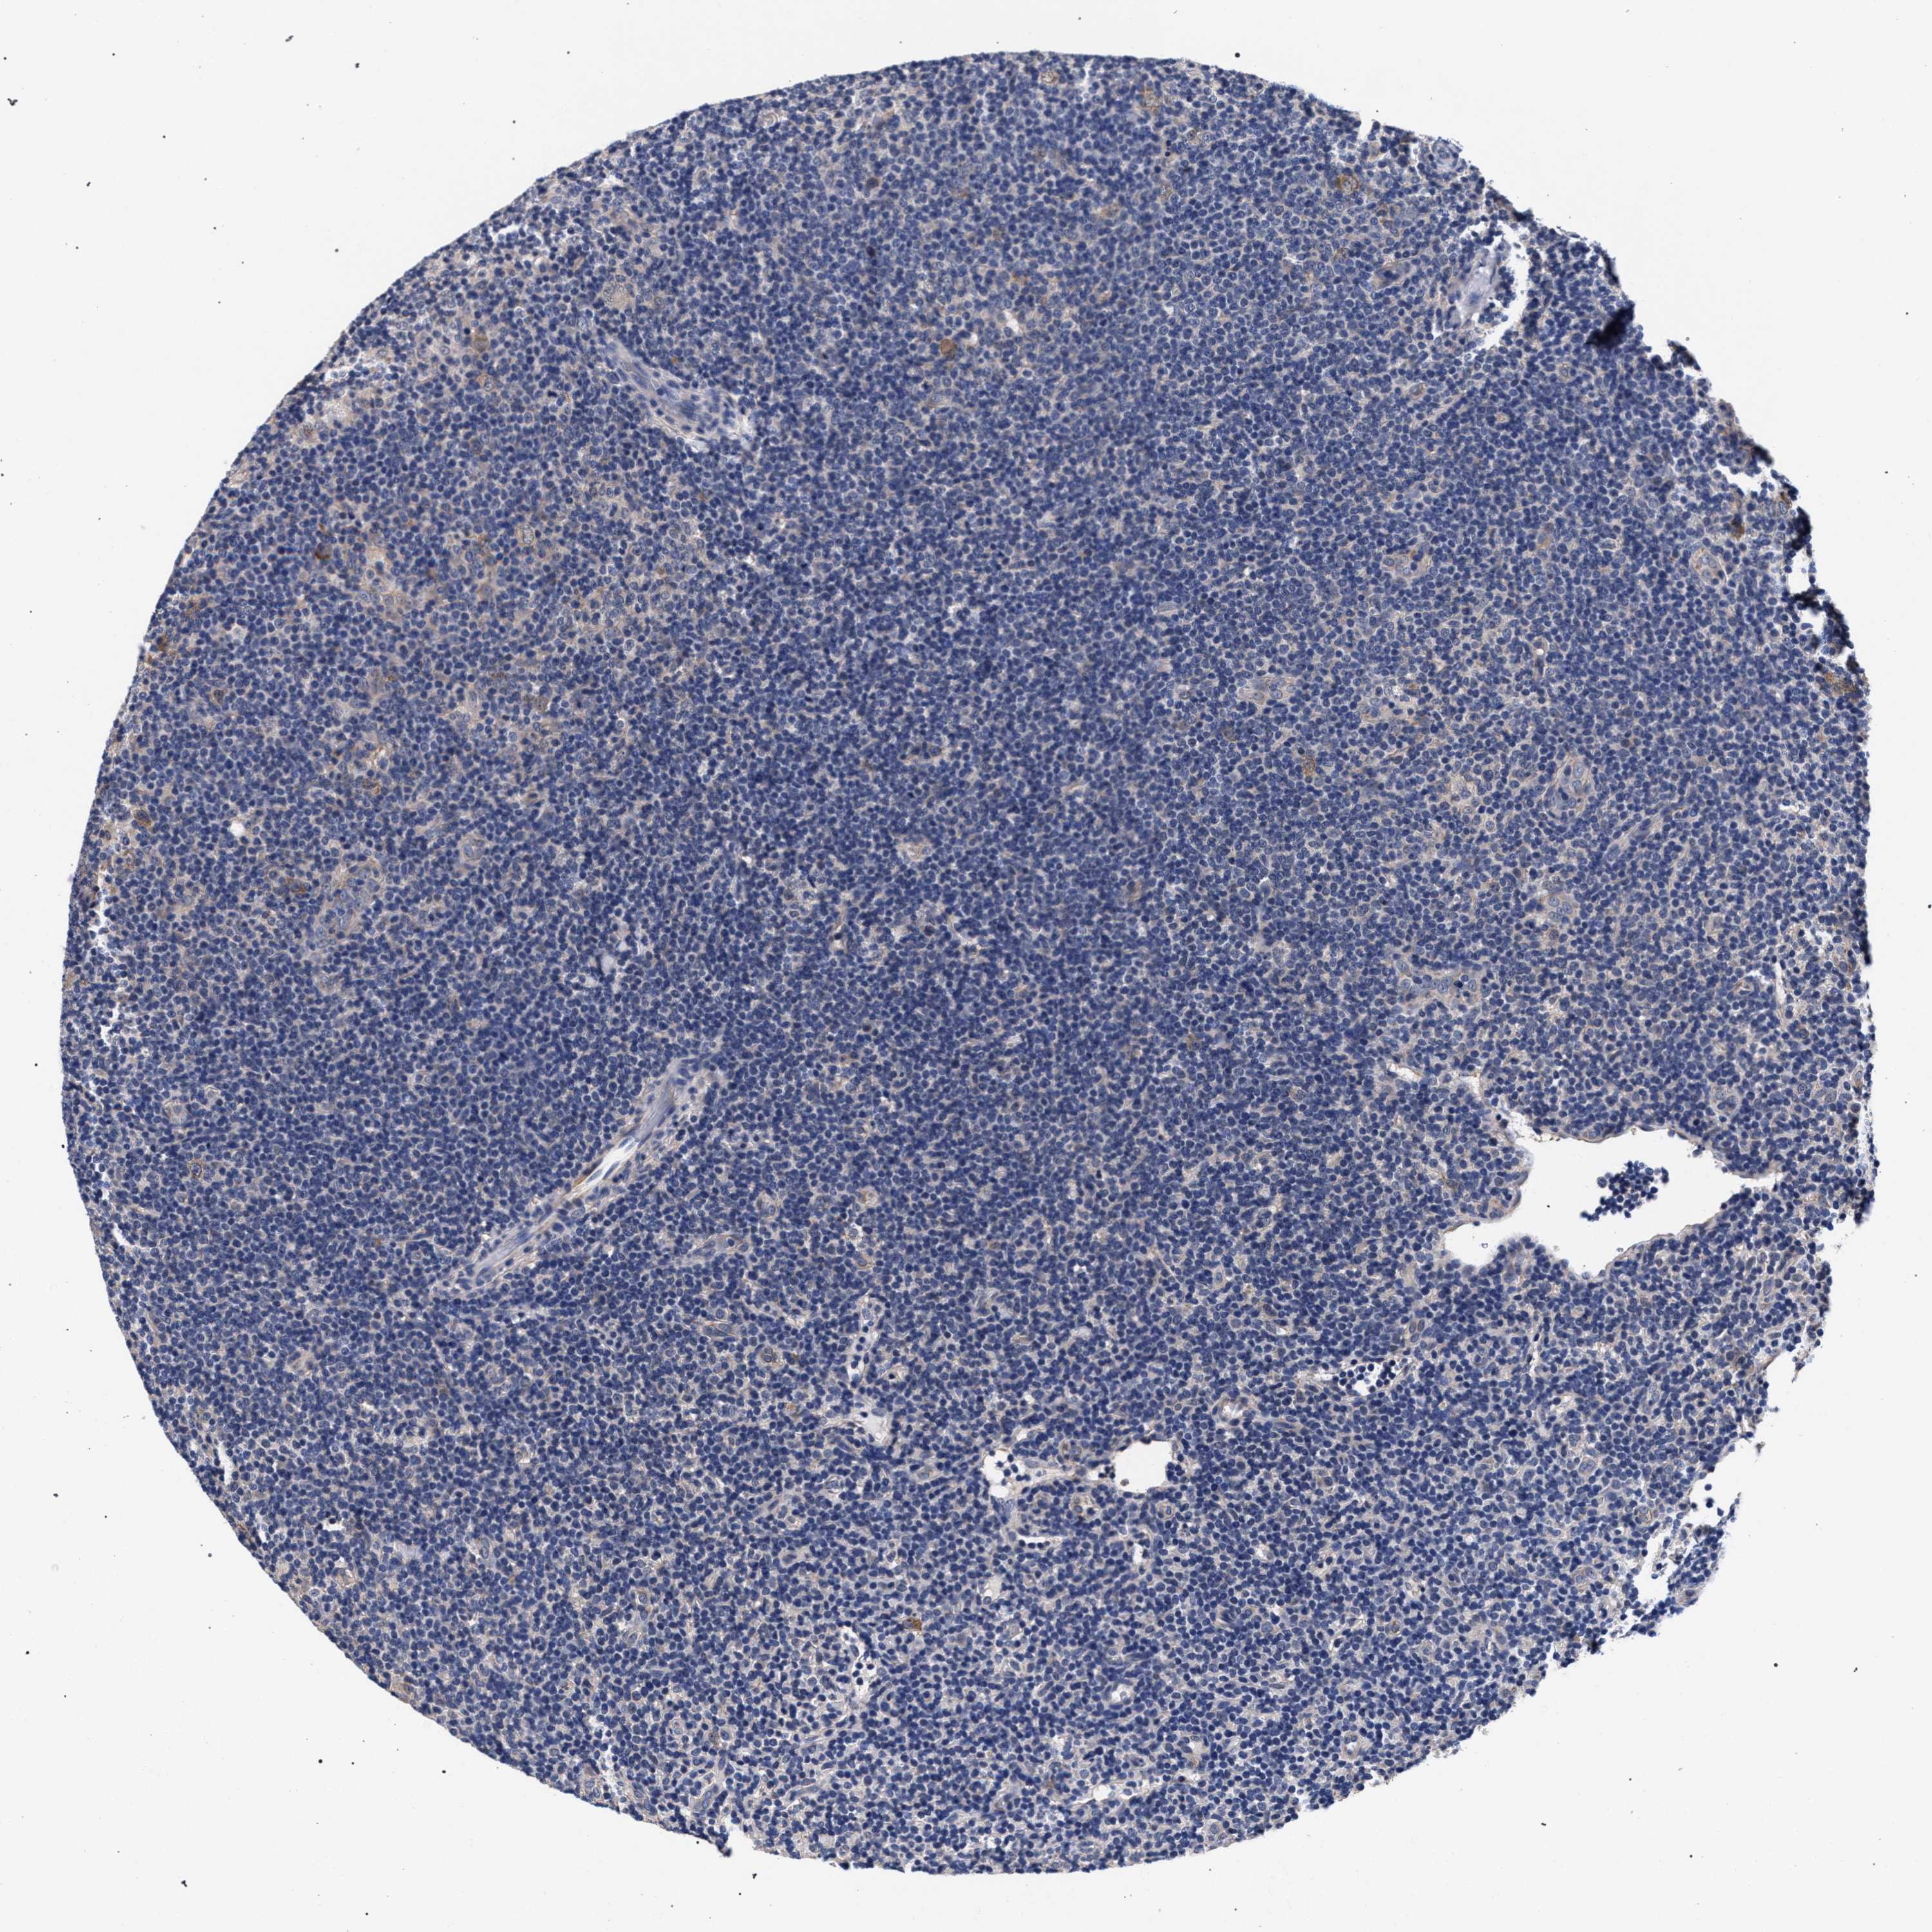

CANCER LYMPHOMA Show tissue menu

LYMPHOMA - Protein expressioni

A mouse-over function shows sample information and annotation data. Click on an image to view it in a full screen mode. Samples can be filtered based on level of antibody staining by selecting one or several of the following categories: high, medium, low and not detected. The assay and annotation is described here.

Each image is clickable and will lead to virtual microscopy that enables deeper exploration of all samples and also displays staining intensity scores, fraction scores and subcellular localization as well as patient and tissue information for each sample.

Antibody HPA019232

Hodgkin's disease, NOS

Malignant lymphoma, non-Hodgkin's type, High grade

Malignant lymphoma, non-Hodgkin's type, Low grade